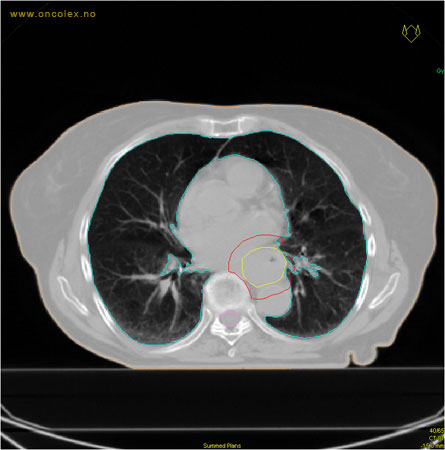

Målvolum

Skisse over hvordan strålefeltet planlegges:

Illustrasjon for målvolum

• GTV (Gross Tumor Volume): Identifisert tumor.

• CTV (Clinical Target Volume) GTV + omkringliggende vev hvor det kan væremikroskopisk spredning.

• ITV (Internal Target Volume): CTV + en indre margin som tar hensyn tilindre bevegelser og endringer av CTV.

• PTV (Planning Target Volume): Innstillingsmargin som inneholder ITV og samtidig tar hensyn til antatte pasientbevegelser, samt variasjoner i pasientopplegging og feltinnstillinger.

• Feltgrense. Tegnes som oftest på kroppen.

ICRU (International Commission on Radiation Units and Measurements)